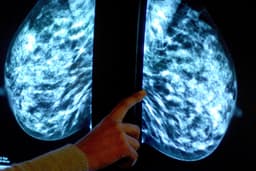

Researchers have pinpointed a significant vulnerability in triple-negative breast cancer (TNBC), a particularly aggressive form accounting for nearly 31% of breast cancer cases in India. This breakthrough offers new hope for patients facing limited treatment options beyond chemotherapy, which often leads to recurrence due to drug-resistant tumor cells.